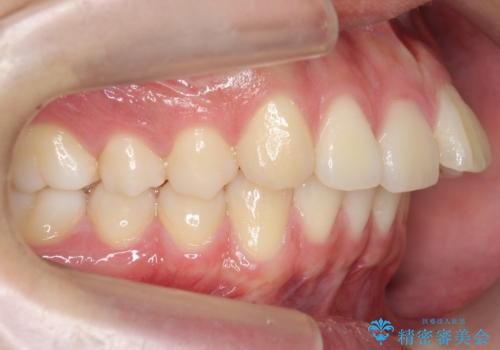

- 出っ歯を主訴に来院。

奥歯の歯ならびのずれが大きく、親知らずを抜いてすべて後ろに下げるか、手前の歯を抜いて前歯を下げるかの2択でした。

時間はかかりましたがしっかり前歯を下げて治療しています。